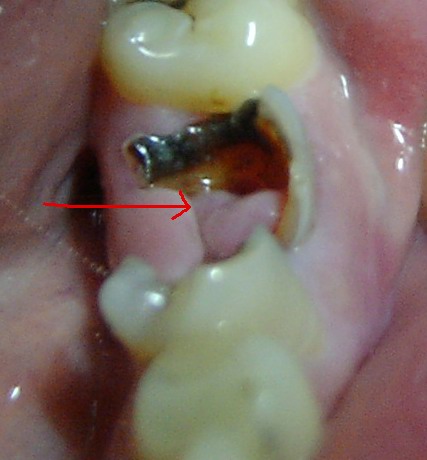

看来是你的牙龈组织长出来的息肉,到医院想办法处理一下,很小的手术

得了牙息肉(有图),能自愈吗?怎么治疗?要拨牙,要手术吗?

最近突然发现牙齿那里长了一个像肉的东西,不痛不痒的,怎么处理?

【图】牙龈息肉图片 患者应该如何治疗?

解析牙龈息肉和牙髓息肉的治疗方法有哪些

问:我这个牙龈息肉严重么?